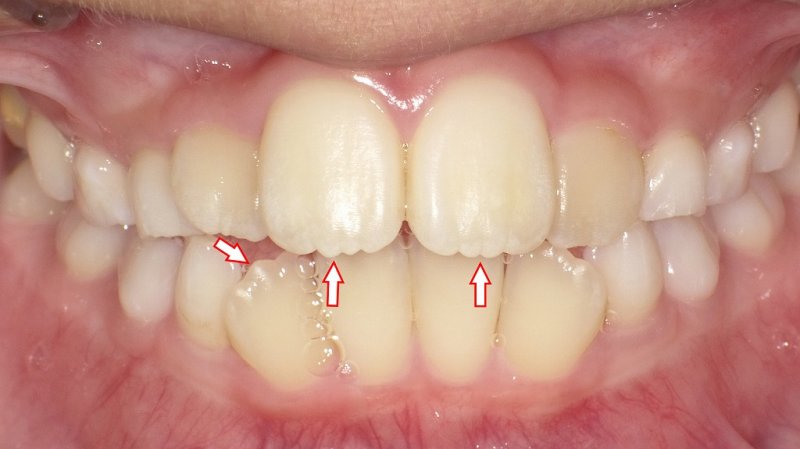

成人におけるギザギザは異常の可能性

一方、成人の歯にギザギザが生じている場合、多くは後天的な歯質の摩耗や破折が原因です。

主な要因は以下の通りです。

- ブラキシズム(歯ぎしり・食いしばり)による咬耗

- 酸蝕症(酸性飲食物や胃酸の影響)による脱灰

- 不正咬合による局所的な過重負担

- う蝕や歯周病による歯質の崩壊

- エナメル質形成不全などの先天異常

これらによりエナメル質が失われると、象牙質の露出や切端の不整が生じ、知覚過敏や破折リスクが高まります。